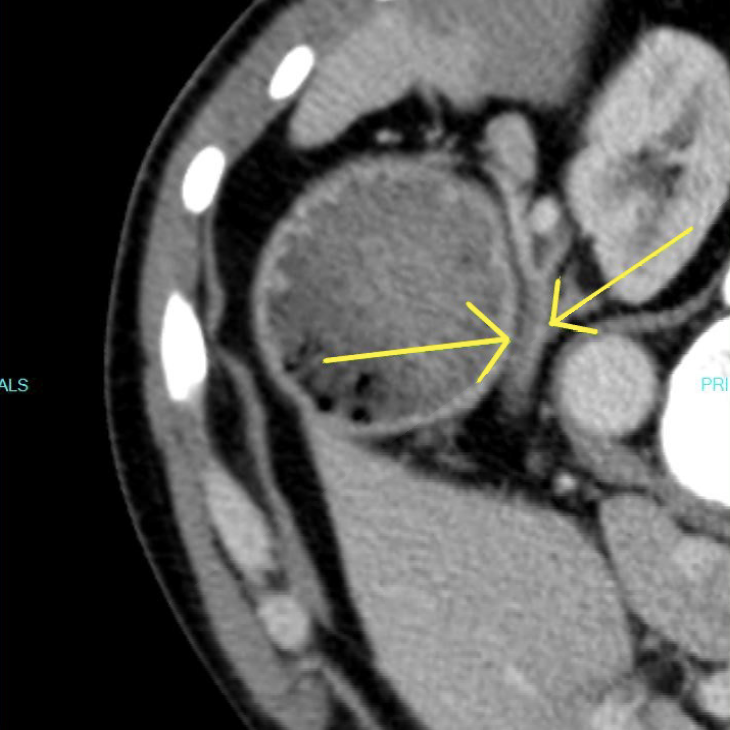

A contrast-enhanced CT scan was completed and revealed stenosis of the celiac trunk and mild bulbous dilatation of the post-stenotic celiac trunk (Figure 1). There was the appearance of a dissection flap that developed into an eccentric hypodense non-enhancing false lumen. This appeared to extend into the common hepatic arterial trunk and the splenic arterial branch, then continued to the splenic hilum (Figure 2 and Figure 3). In addition, there was a large splenic hypo-density involving almost one-third of the central spleen (Figure 4). The findings were consistent with an acute dissection of the splenic and hepatic arteries, along with splenic infarction of the central one-third of the spleen. A differential diagnosis of arcuate ligament syndrome was also considered, given the significant scoliosis seen on scout film of the CT scan (Figure 5).